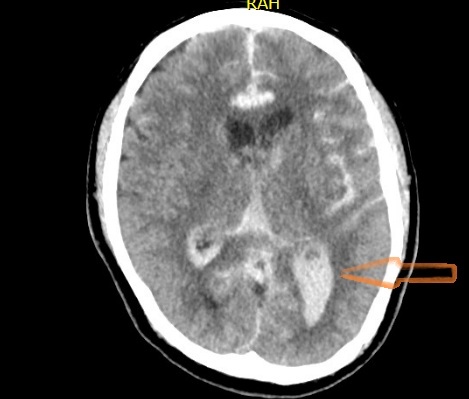

Figuur 4 – CT-hersenen met op de pijl

Dwarsdoorsnede CT hersenen. De rode pijl geeft aan dat er ook doorbraak van bloeding in het ventrikelsysteem is waar te nemen.